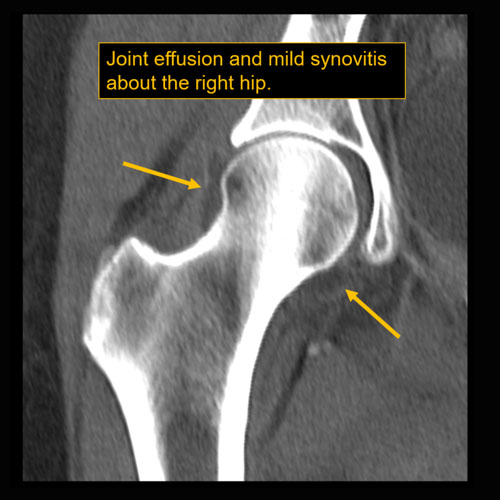

Section 1 Submit Findings CB1118 Findings Limitations There is patient motion or other limitations. Yes No Skin/Hypodermis There is edema or hyperenhancement. Yes No There is soft tissue ulceration or sinus tract. Yes No There is gas or foreign body. Yes No There is confluent hypoenhancement to suggest phlegmon, suppuration, abscess, or drainable fluid collection. Yes No Investing/Intermuscular Fascia There is edema, thickening, or hyperenhancement. Yes No There is hypoenhancement or gas along the fascia. Yes No There is bulging of the fascia. Yes No Muscles There is edema or hyperenhancement. Yes No There is hypoenhancement, lack of enhancement, or organized fluid collection. Yes No There is fatty atrophy. Yes No Bones There are fractures. Yes No There is periosteal reaction, osseous destruction, or focal demineralization to suggest osteomyelitis. Yes No There is cloaca, sequestrum, or involucrum. Yes No There is a subperiosteal or intra-osseous abscess. Yes No Visualized Joints There is a joint effusion. Yes No There is malalignment, degenerative changes, or other gross internal derangement. Yes No Miscellaneous There is tenosynovitis. Yes No Major visualized vascular structures are abnormal. Yes No Major visualized nerves are abnormal. Yes No